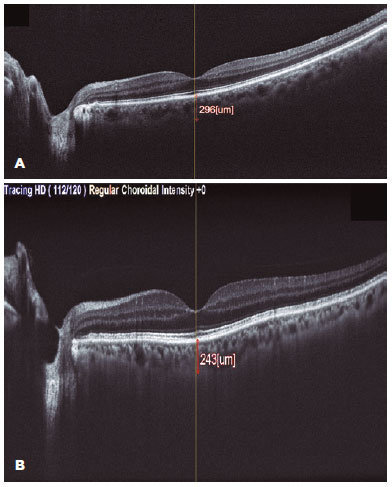

In the SFCT evaluation, statistically significant difference was noted among the groups 1, 2, and healthy controls (p<0.001). In post-hoc analysis, the mean SFCT was 250.24 ± 68.34 µm in group 1 and 216.72 ± 71.24 µm in group 2; this difference was statistically significant. The mean SFCT in the control group was 273.64 ± 77.68 µm, which was significantly greater than that in groups 1 and group 2. Figures 1A and 1B illustrate the SCFT images from a healthy control and a group 1 patient. The average pRNFLT was 100.34 ± 8.24 µm in group 1, 95.44 ± 6.67 µm in group 2, and 102.34 ± 8.24 µm in the control group. Figures 2A and 2B depict the pRNFLT images of 1 subject each from the control group and from group 2. The mean pRNFLT was significantly lesser in group 2 patients than in group 1 patients and the control subjects (p=0.042 and p=0.036, respectively), albeit the difference in the thicknesses between group 1 and the control group was not statistically significant. Analyses of the pRNFL quadrants parameters revealed that all quadrant thicknesses in group 2 were significantly lesser than those in group 1 patients and control subjects. The comparative analyses are depicted in table 2.